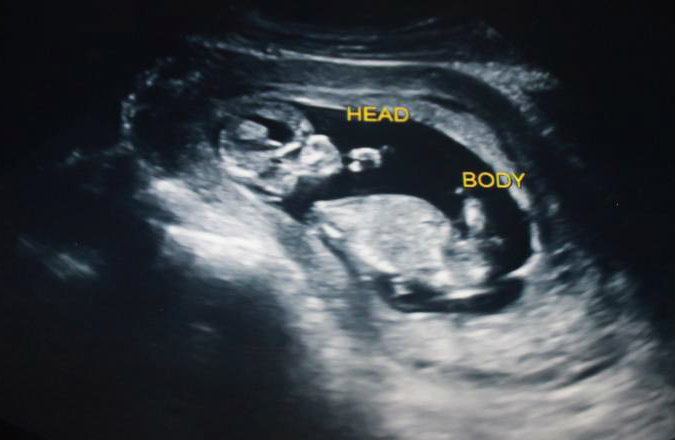

13 week ultrasound - can you see a nub? Lovemy4, please help! :)

I had an ultrasound yesterday at 12 weeks 5 days. Baby was measuring 13 weeks 3 days. Heart rate was 167. Baby was moving around a lot and I'm not sure if I ever saw a clear nub at all. :( I did see a potty shot and didn't see anything protruding between the legs at all, I saw what looked like a white spot between the legs (didn't see three lines, but wondering if it may have been girly parts seen from a distance, it wasn't a very close-up shot). My symptoms this pregnancy have been identical to my previous girl pregnancy. I don't have a gender preference, but this just feels like a girl to me. Any thoughts? If the nub isn't visible, what do you think based on skull shape? I thought the profile reminded me of my daughter, she had a rounded forehead like this, and my son's was very straight.